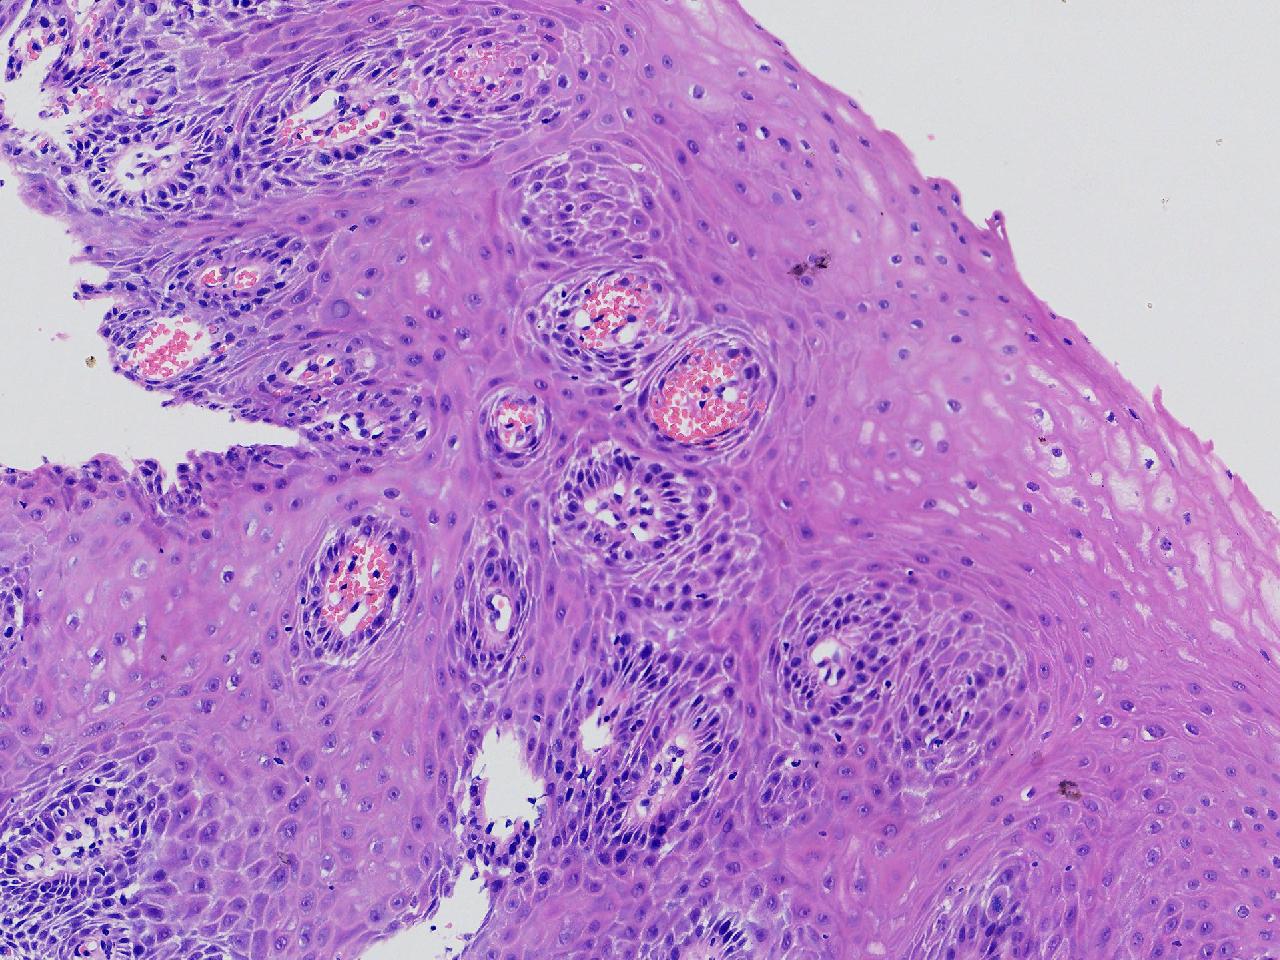

男,62岁,贲门口齿状线上见条状糜烂,活检1块,质软。

贲门口活检

灰白色不整形软组织1块,直径0.2厘米。

图1

鳞皮乳头状增生伴慢性炎。